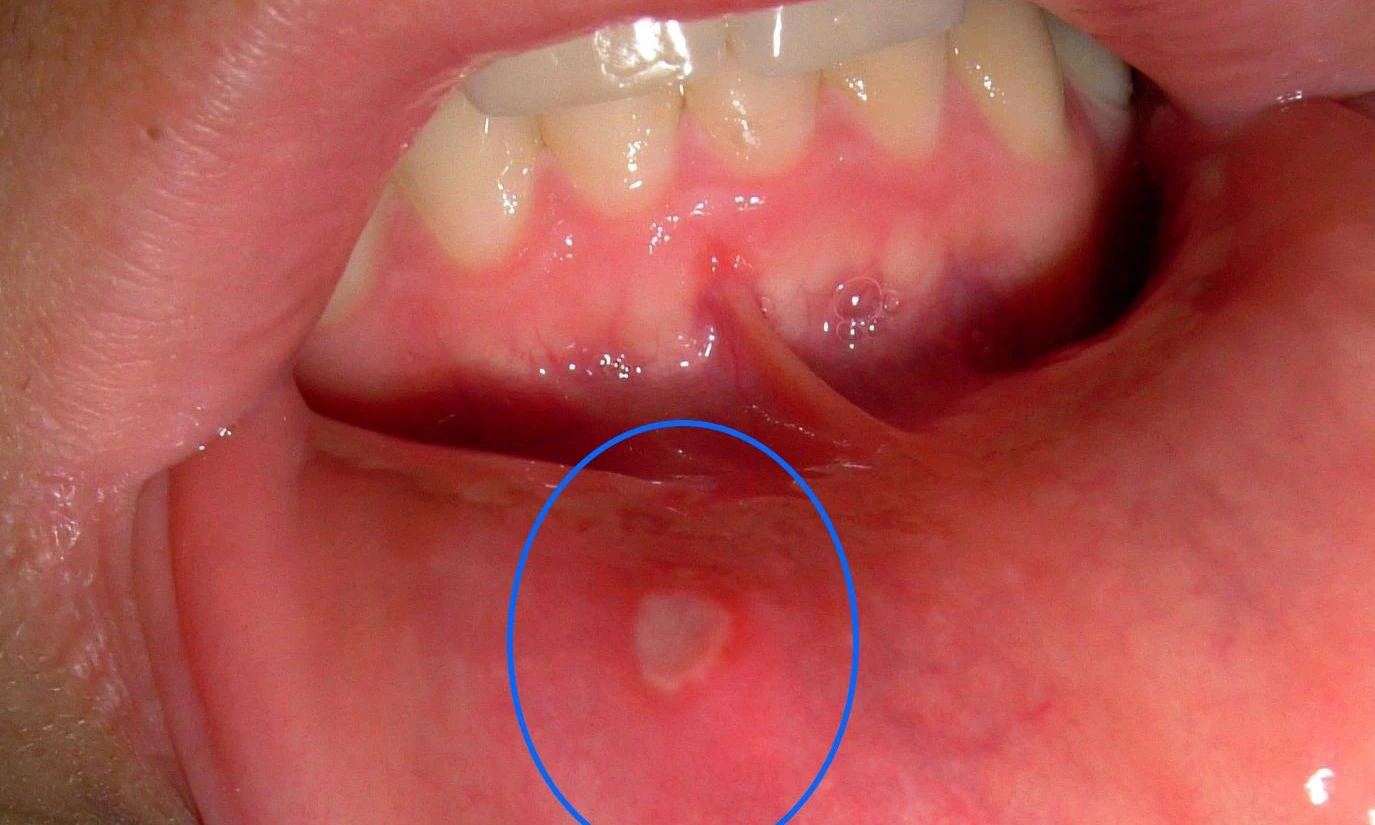

(Kiến Thức) - Hầu như ai cũng từng một vài lần khốn khổ vì bệnh nhiệt miệng. Hãy bỏ túi vài cách chữa nhiệt miệng tại nhà hiệu quả nhanh để áp dụng khi cần.

Nguyên nhân của bệnh nhiệt miệng là do sự suy giảm hệ thống miễn dịch, khiến vi khuẩn dễ dàng tấn công vào khoang miệng, gây ra những vết lở loét ở lưỡi, nướu và các vị trí khác trong miệng. Ngoài ra bệnh này cũng có thể xảy ra khi cơ thể bị thiếu hụt nước dẫn đến cơ nhiệt tăng cao, nóng trong người.